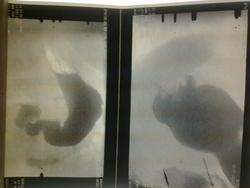

Женщина1935 года рождения.Жалобы на бысттрую утомляемость,головокружение.Hb=46.Прошла курс лечения в гематологии(Hb был 44.после курса терапии 70.но через месяц опять Hb=46.11 10 12 Rtg-скопия желудка (Объём дна желудка) 15.10.12 ФГДС - Патологии не обнаружено. 15.10.12 Rtg-скопия желудка(ещё раз) -Грыжа пищеводного отверствия диафрагмы? Объём? Очень важно ваше мнение!

помоему свод деформирован и не расправляется

Есть объем, нет объема - норму не напишешь (см. снимок 4). Снимков много, но нужны еще. На повторном исследовании, тем более после отрицательной гастроскопии, надо было дать "шипучку" (лимонную кислоту запить содой, разведенной в стакане с бариевой взвесью). Для изучения свода нужен еще левый боковой снимок (после обмазывания барием в положении лежа). На ГПОД нужен снимок в положении лежа на животе с приподнятым левым боком. Но это на будущее. Как поступить в данном случае? Написать "можно думать, нельзя исключить" (

3.Кстати, смещение газового пузыря медиально, вкупе с другими изменениями, далеко не норма.

"Шипучка" была.Снимок увы не сделал.Свод расправился частично,но очень уж ровные контуры были.

Наверное, что-то смещает газовый пузырь извне. УЗИ делали?